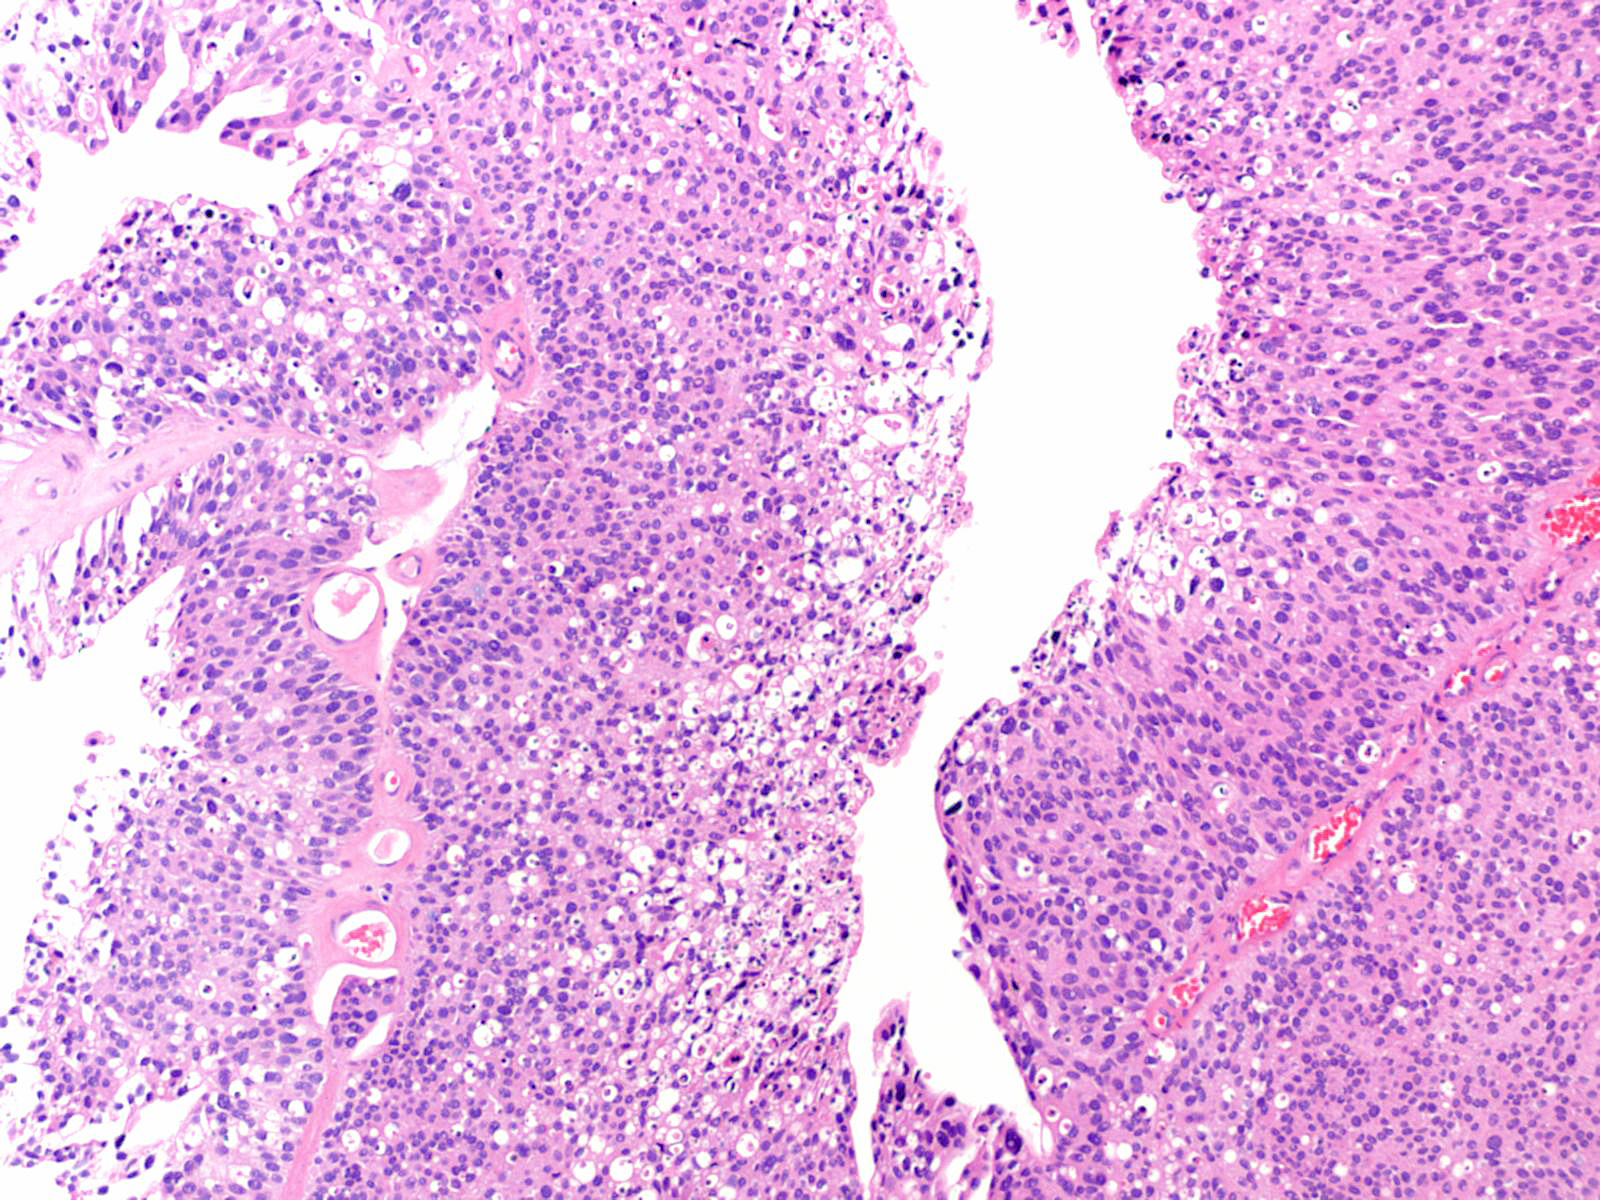

Bladder Papillary Lesions

Case ID: 212